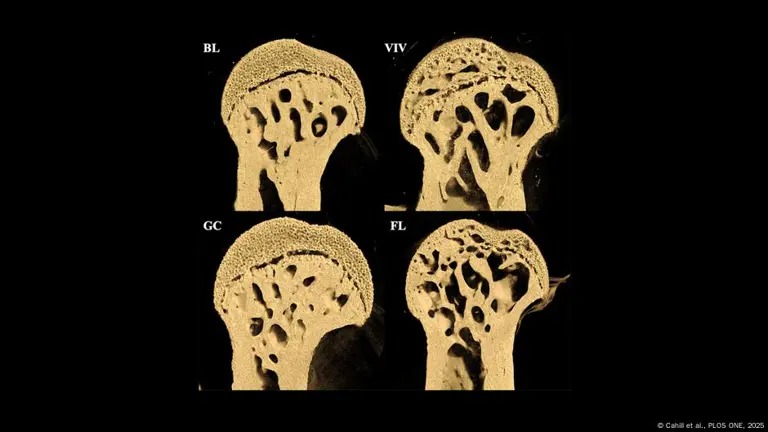

La NASA envió ratones al espacio como parte de un estudio sobre los efectos de la microgravedad en los seres vivos. Después de permanecer 37 días en órbita, los ratones experimentaron una notable degradación ósea, especialmente en los fémures, en comparación con los ratones de control que permanecieron en la Tierra. Este hallazgo resalta el impacto negativo de la falta de gravedad sobre los huesos, un aspecto crítico para los astronautas que realizan misiones prolongadas fuera de nuestro planeta.

Uno de los principales problemas que enfrenta la NASA con las misiones prolongadas al espacio es la pérdida de masa ósea. En condiciones de microgravedad, el cuerpo humano, así como el de los ratones utilizados en este estudio, experimenta cambios biológicos que resultan en un debilitamiento de los huesos. A lo largo de los estudios, se ha demostrado que, si no se toman medidas para mitigar estos efectos. Los astronautas podrían enfrentar serias dificultades a su regreso a la Tierra.